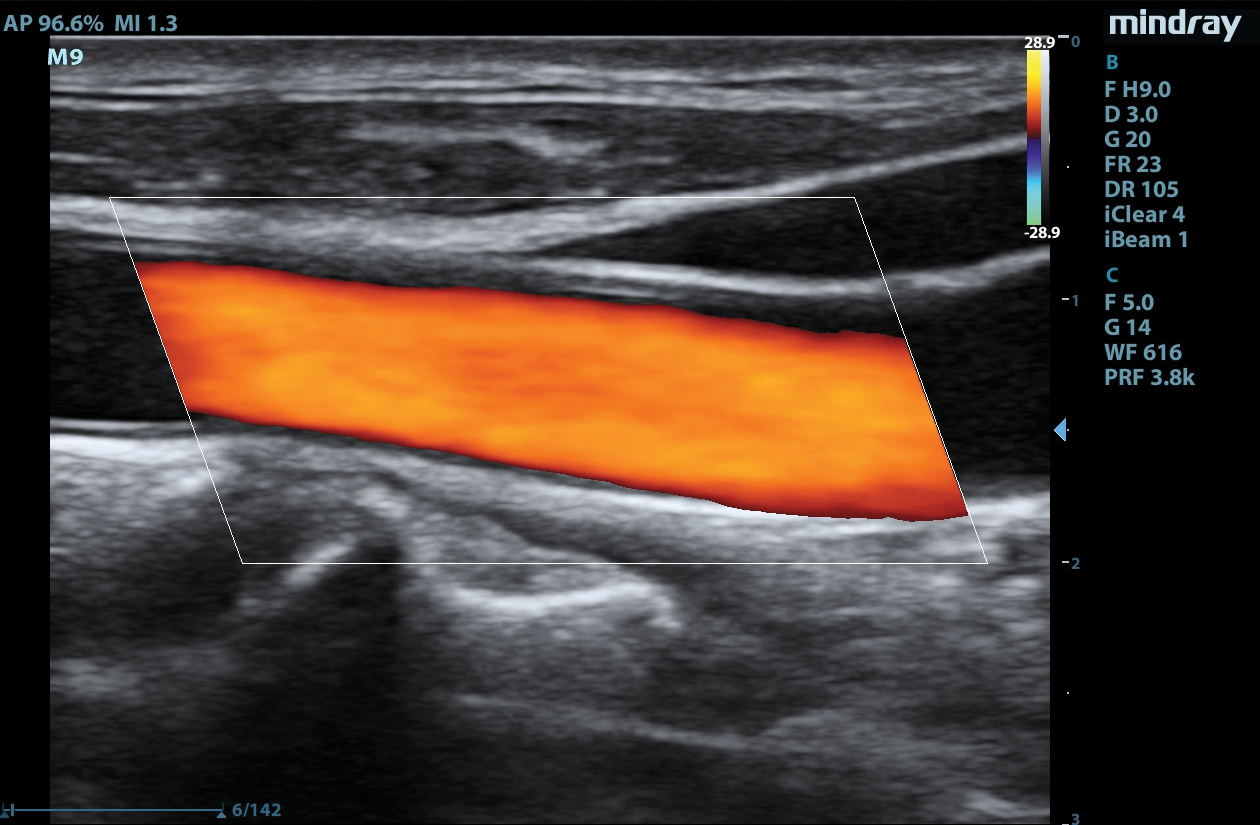

The M9 Ultrasound System Ruby Edition offers a fully-featured, compact ultrasound solution for your most challenging point-of-care exams. Delivering image clarity and advanced capabilities previously only available on larger, cart-based systems, the M9 System defines the new standard for intelligent performance in a mobile, laptop design.

Equipped with single crystal transducers and 3T™ technology for a wide range of exams, the M9 System is a versatile platform for advanced imaging in the vascular lab, emergency departments, critical care environments, and anesthesia practices. The System’s slim profile and ergonomic design allow for effortless flexibility and mobility. Whether it be ultrasound guided procedures at the patient’s bedside or transesophageal echocardiography (TEE) imaging in the critical care unit, this platform can do it all.